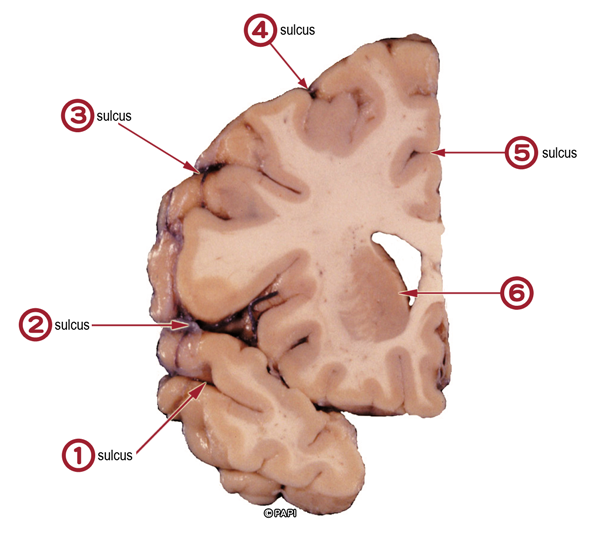

Cerebrum(coronal cut)

superior temporal sulcus

lateral sulcus

inferior frontal sulcus

superior frontal sulcus

cingulate sulcus

caudate nucleus